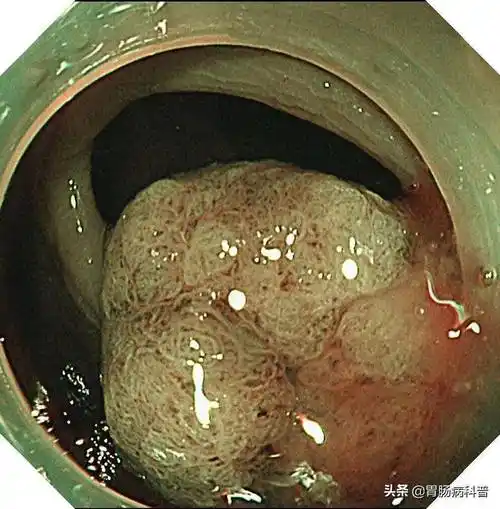

【健康百科】肠息肉离癌有多远?_政务_澎湃新闻-the paper

一文读懂肠息肉——为啥会长肠息肉?严重吗?如何治疗?怎样预防_肠道_

肠息肉大便图片(肠内若有) - 赤虎壹号